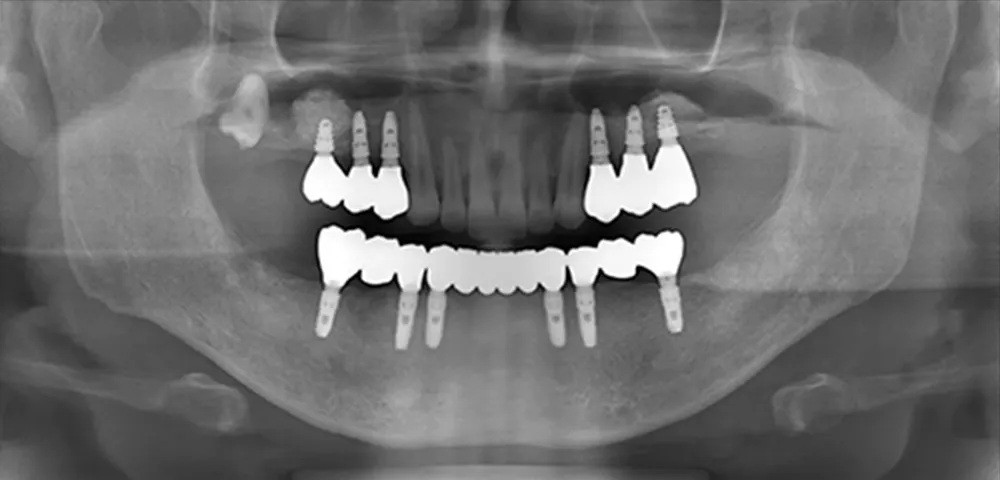

さまざまなトラブルやリスクを伴うインプラント治療には、患者様一人ひとりの骨や健康状態に応じた専門的な診断と高精度な技術が求められます。国内外で研鑽を積む理事長が、より安全で精密な治療をお届けします。骨が少ない、持病があるなど、一般の歯科医院では対応が難しい方も一度ご相談ください。

精密な治療を実現する体制

サージカルガイドを

駆使した治療 -

通算911本の(※2024実績)

インプラント埋入実績 -

難症例に対応する

国内屈指の技術骨補填材「A-Oss」

を用いた

世界基準の骨造成術